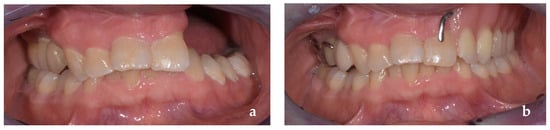

2. Clinical Case Presentation

2.2. Prosthetic Management

3. Results